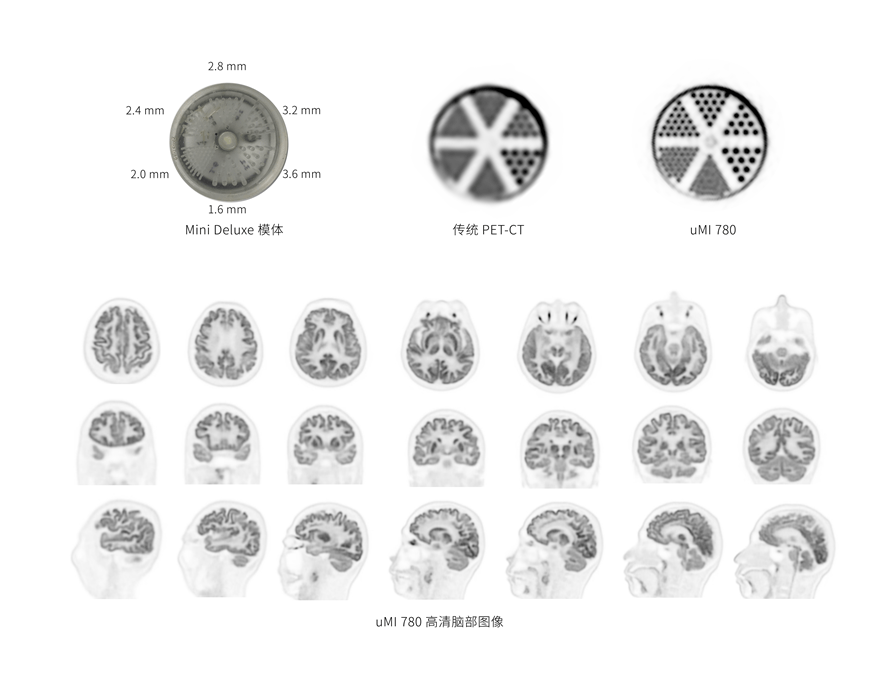

超清显像

2.9mm

超清NEMA分辨率成像

TOF + PSF

600 x 600

超大矩阵,高精度超清重建